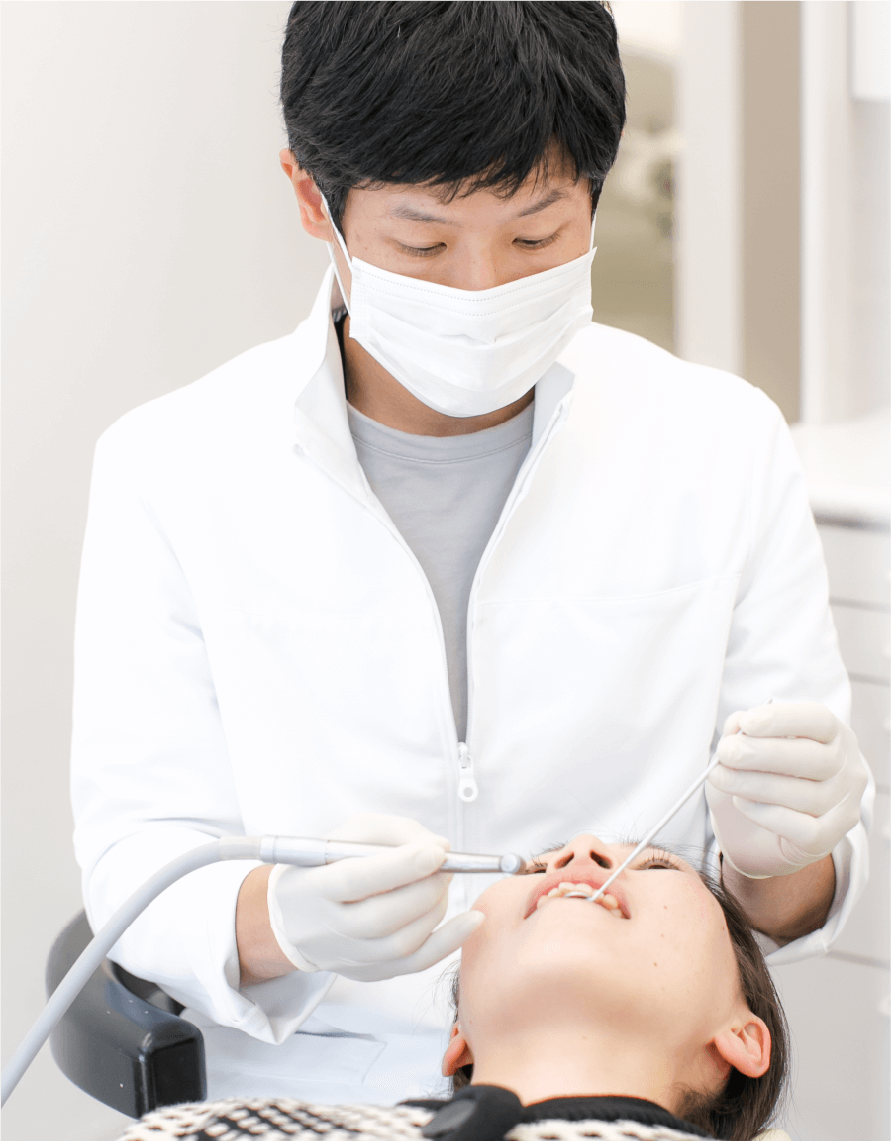

診査・診断

診査・診断口腔管理の徹底で歯の現状を診る

歯の疾患の進行度に合わせて、適切な治療を行うことが大切です。数十年の経過を見極め、できるだけ削らず、抜くようなことがないように予見し、口腔管理を行っていくことを方針としています。